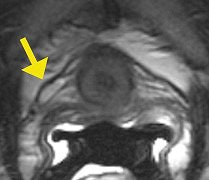

| Visualization of the laxity of the right periurethral ligament (arrow) on endovaginal MRI in a woman with UH. Image courtesy of Dr. Katarzyna J. Macura, Ph.D., Johns Hopkins University. |